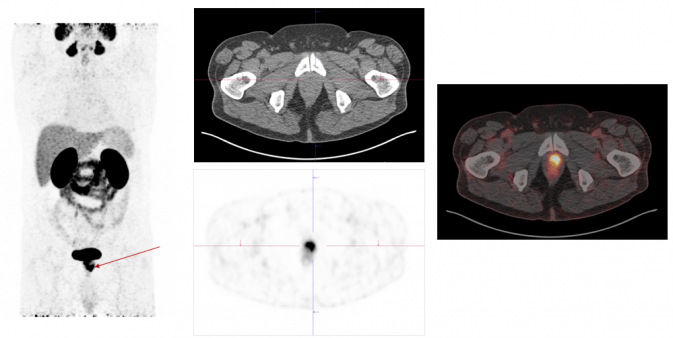

Ga-68-PSMA

Ga-68-PSMA-PET is a nuclear medicine procedure that can be used to image prostate cancer. .

Exemplary case study on PSMA-PET/CT diagnostics: